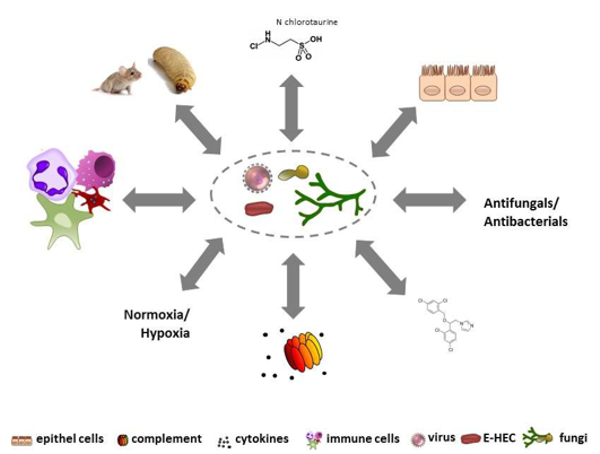

Infectious diseases are becoming one of the most frequent causes of death in the world; at present, we face bacteria and fungi that are developing resistance to antibiotics and antimycotics as well as the fact that an increasing number of emerging pathogens are spreading worldwide. Understanding the biological principles underlying the mechanisms by which infectious agents adapt and undermine the defence mechanisms of a host is critical to fighting diseases. HMM conducts basic and translational research into molecular mechanisms of pathogenesis of bacterial, viral, or fungal infections and strategies for prophylaxis and treatment. HMM’s mission is to coordinate and strategically align translational infection research with the aim of developing new diagnostic, preventive and therapeutic methods to treat infectious diseases. To achieve this, HMM has formed thematic translational units of scientists, each dedicated to one specific pathogen or infectious disease. HMM is one of the largest diagnostic microbiology laboratories in Austria and has an average sample throughput of 250,000 specimens per year. It is associated with all the major hospitals in Tyrol, and therefore holds a key position in the diagnostic laboratory landscape of Austria. The working groups of Reinhard Würzner, Doris Wilflingseder and Wilfried Posch cover the topic “Exploiting immune response”, the working groups of Michaela Lackner and Cornelia Lass-Flörl with Cornelia Speth and Ulrike Binder investigate fungal infections. “N-chlorotaurin” is the main research focus of Markus Nagl, and Peter Kreidl covers the topic of public health. Astrid Mayr is connected with the CD Laboratory. The mission of HMM is to bridge the gap between basic and translational research into microbial pathogenesis (Fig. 2).

CD Fungus is attempting to unravel the scientific questions raised, by implementing 3 modules that will ultimately advance our understanding of fungal pathology, improve diagnosis and treatment of mucormycosis, and enhance patient outcome and safety in terms of prevention of nosocomial and hospital-related infections.